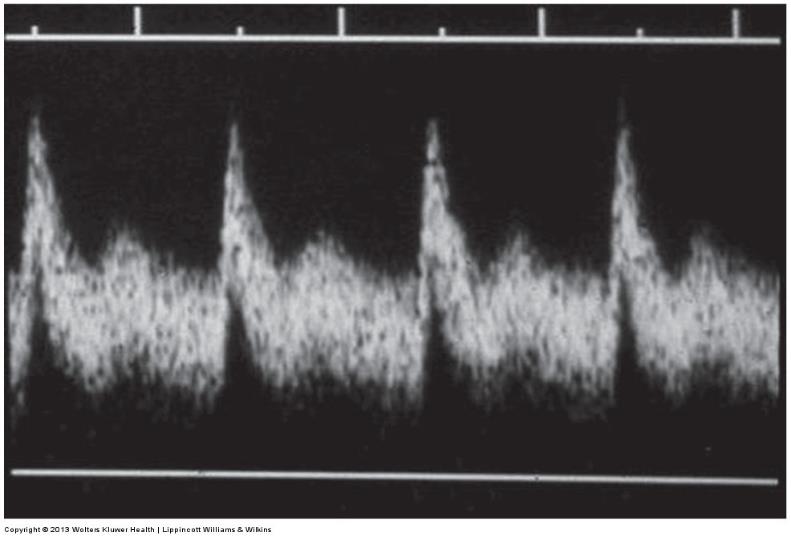

normal multiphasic waveform taken from SFA

an abnormal waveform illustrating constant forward flow throughout the cardiac cycle in addition to a delayed upstroke . distal to high-grade stenosis or occlusion

waveform dusiplaying a normal systolic upstroke with constant forward flow through diastole

an abnormal high resitance waveform with only antegrade flow through systole . this is observed proximal to a near occlusion or occlusion